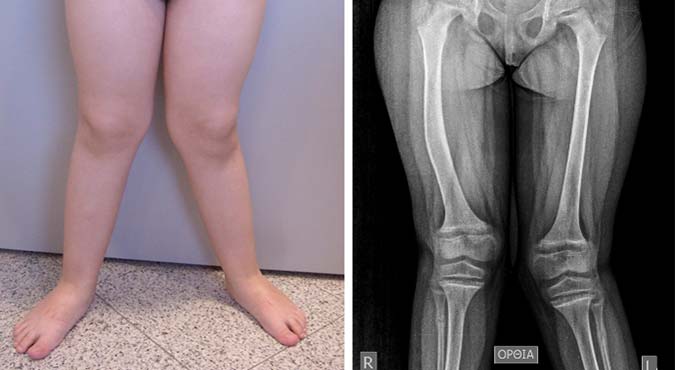

Βλαισογονία ονομάζεται η πάθηση όπου όταν το παιδί βρίσκεται στην όρθια θέση, τα γόνατα εφάπτονται και οι κνήμες αφίστανται.

Εικόνα βλαισογονίας, με διεύρυνση των επιφυσιακών πλακών των μηριαίων και των κνημών και διαυγαστικές ζώνες (Looser) στο άνω άκρο της περόνης άμφω.